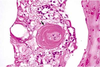

Retina from an adult cat with acquired blindness

Lost photoreceptor and outer nuclear & plexiform layers

Morphologic diagnosis: Retinal atrophy (& degeneration)

Cause:

Enrofloxacin toxicity

histo can’t tell you the etiology

Retina from a horse with increased IOP (glaucoma)

Loss of nerve fiber and ganglion cell layers, but excellent preservation of photoreceptors and outer nuclear layer

MDx: retinal atrophy

Causes of retinal detachment (separation)

Exudative

– Choroiditis, retinitis – Hemorrhage

– Neoplasm

• Tractional

– maturation of fibrin in vitreous (fibrous adhesions between ciliary bodies = “cyclitic membrane”)

Usually due to inflammation

Retinal detachment due to effusion from the growth of metastatic lymphoma within the choroid and subretinal space

Retinal detachment (separation)

Consequence = retinal degeneration & atrophy

Separates between neural and pigmented layers